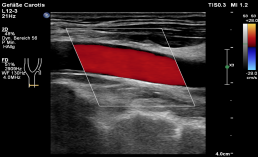

Mit einem hochmodernen, hochauflösenden Ultraschall werden die Halsschlagadern (A. Carotis) untersucht und somit schon Jahre vor einem möglichen Schlaganfall krankhafte Veränderungen festgestellt. Die Ablagerungen in den Schlagadern (Arteriosklerose) zeigen sich anfangs durch die Verdickung der inneren Gefäßwandschicht (Intima-Media-Dicke). Die Messung der Intima-Media-Dicke ist schnell, einfach und schmerzfrei.

Untersuchung der Halsschlagadern (A. Carotis)

Messung der Intima-Media-Dicke (Gefäßwandschicht) der Halsschlagadern (A. Carotis)